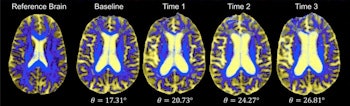

DSEG images for axial brain slices of SVD patients. Images in the SVD brain are shown over three time points with DSEG Θ angle scores for microstructure changes. Increases in Θ show substantial DSEG changes in brain microstructure over time with increasing brain damage. © 2017 The Authors (CC BY-NC-ND 4.0).

The developed methodology utilizes a diffusion tensor image segmentation (DSEG) technique, combining several MRI-detectable SVD markers to produce a sensitive singular score for disease severity and brain damage. This enables monitoring of alterations in brain microstructure over time via a single angular measure -- DSEG Θ.